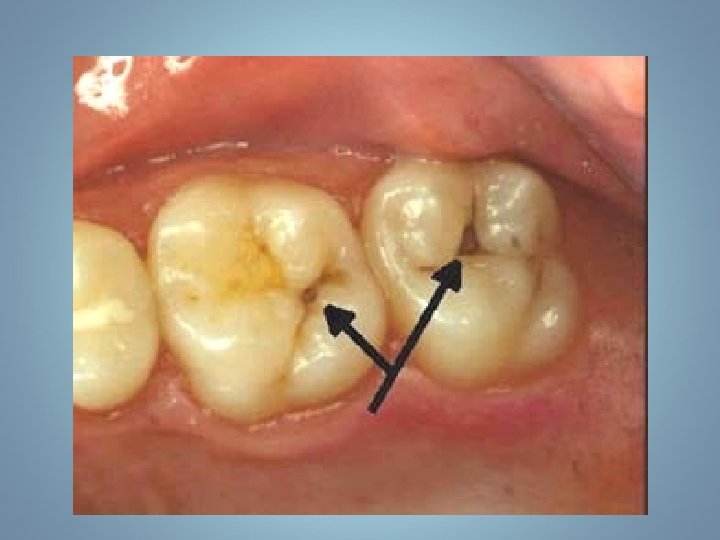

• Propagation dans la dentine est plus facile car…

De l’émail vers la dentine… • Forme un cône plus large… • Dentine moins calcifiée • Fibres de Tomes ne sont pas calcifiées • Anastomoses entre les tubulis

Propagation dans la dentine. Forme un cône plus large que dans l’émail.